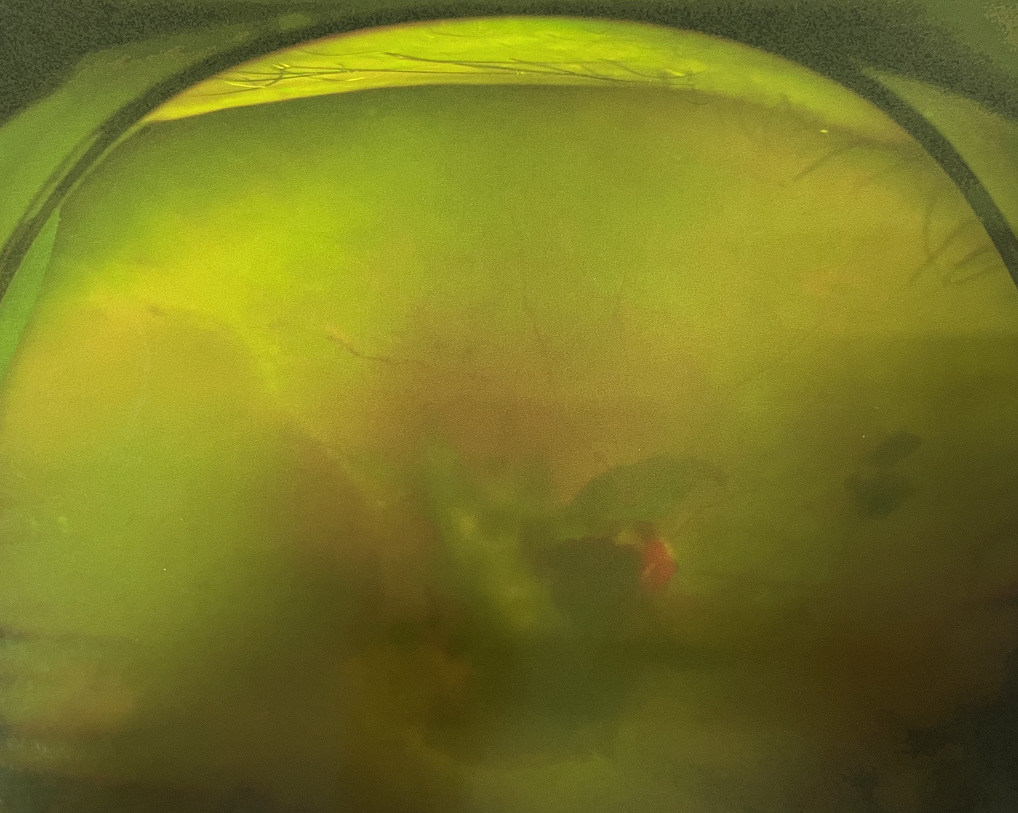

眼底出血多指玻璃體內(nèi),眼睛更深處的視網(wǎng)膜出血。通常情況下,肉眼難以發(fā)現(xiàn)眼底出血,而且發(fā)病初期眼睛也無(wú)明顯癥狀,只有借助專業(yè)的眼底檢查儀器才能觀察到異樣。那么眼底出血嚴(yán)重嗎?

誘發(fā)眼底出血的原因眾多,常見(jiàn)的有全身性血管病和血液病、視網(wǎng)膜血管異常、機(jī)械性阻塞、炎癥性疾病或免疫復(fù)合物侵犯血管壁等。

眼底出血嚴(yán)重嗎?其中,“三高”患者、高度近視患者和滲出性或濕性老年黃斑變性患者是眼底出血的高發(fā)人群。

醫(yī)生提醒,一旦眼睛出現(xiàn)視力下降、視物變形、視野缺損或眼前有黑影等視覺(jué)“異常”的情況,應(yīng)及時(shí)到醫(yī)院進(jìn)行眼底檢查,及早發(fā)現(xiàn),及早治療,以免貽誤病情。

眼底出血嚴(yán)重嗎?對(duì)于已出現(xiàn)黃斑水腫、視網(wǎng)膜新生血管的患者,根據(jù)眼底血管造影、oct等檢查結(jié)果,給予玻璃體腔注射抗VEGF藥物及激光治療,可以減輕黃斑水腫,使視網(wǎng)膜新生血管消退,以免進(jìn)一步發(fā)生玻璃體出血、視網(wǎng)膜脫離等嚴(yán)重并發(fā)癥的出現(xiàn)。對(duì)于玻璃體出血者,傳統(tǒng)認(rèn)為玻璃體出血3-6個(gè)月不吸收再進(jìn)行手術(shù)干預(yù),但近年來(lái)因?yàn)轱@微手術(shù)設(shè)備及玻璃體切割技術(shù)已非常成熟,故對(duì)于1個(gè)月不吸收的玻璃體出血者就可以考慮手術(shù),即手術(shù)時(shí)機(jī)應(yīng)該具體情況具體分析,因人而異。